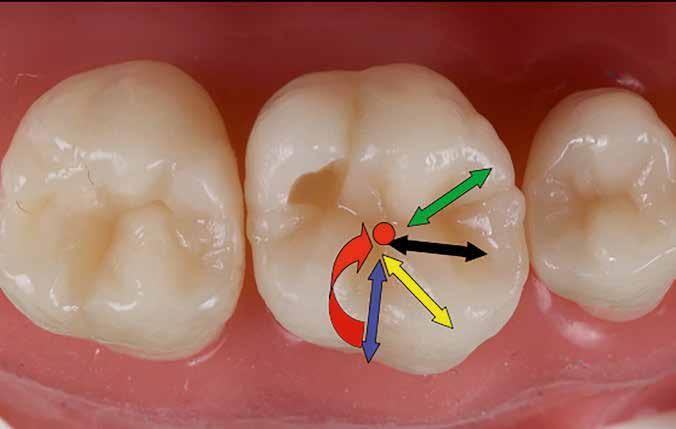

Posselt az állkapocs funkcionális mozgásait a mandibula határmozgásainak görbéjével (Posselt-féle diagram) írta le, amely három térbeli síkra bontható (1. ábra): sagittális, frontális és horizontális. Ebből következik, hogy a fogak dinamikus kölcsönhatása is három dimenzióban értelmezhető [7].

Az egyes csücskök háromdimenzóban végzett, funkcionális mozgáspályáinak összességét nevezzük okkluzális iránytűnek (2. ábra). Az okkluzális iránytű minden csücsök esetében egyedi (a rajta lévő bemélyedések és kiemelkedések szempontjából), és azt a csücsöknek a mandibula condylusának forgásközéppontjához viszonyított helyzete határozza meg.

Az okkluzális iránytű leírásához használt terminológia a The Glossary of Occlusal Terms-ből származik, amelyet a The Glossary Committee of The International Academy of Gnathology állított össze [8]. Fontos megjegyezni, hogy a mandibula mozgásai rágás és nyelés során mindig a maximális interkuszpidációs helyzetből indulnak ki, és oda is térnek vissza.

Ezek a mozgások a következők:

• PROTRUSIO (fekete) – az állkapocs előrefelé irányuló mozgása;

• LATEROTRUSIO (kék) – oldalirányú vagy kifelé történő mozgás;

• LATEROPROTRUSIO (sárga) – kifelé és előre irányuló mozgás kombinációja;

• LATERORESURTRUSIO (piros) – kifelé, hátrafelé és felfelé irányuló mozgás. Ez a mozgás Bennett-mozgásként ismert, Norman G. Bennett (1870–1947) után elnevezve;

• MEDIOTRUSIO (zöld) – mesiális oldalirányú, befelé történő mozgás, amely lehetővé teszi az ellenkező oldali condylus lefelé/előre irányuló mozgását [9].

Az iránytű középpontja (az IKP-ben létrejövő érintkezés) körül található egy kisebb szabad zóna, amely lehetővé teszi az antagonista csücsök mozgását a „hosszú centrikus” (Long Centric vagy Freedom in Centric) tartományban [10]. Ez képezi a Polz-féle biomechanikai wax-up [11] alapját, amelyre a DeVreugd-féle okkluzális iránytű is épül. Jelen publikáció célja egy dinamikus alapú, ésszerű megközelítés bemutatása a hátsó fogak direkt kompozittal történő restaurálásához, amelynek eredményeként a rétegezést követően csupán minimális utólagos korrekcióra van szükség. A szerző a rövidebb, lényegre törő bemutatás kedvéért a felső első molárisra fókuszál. Ezt a fogat azért választotta, mert rágás közben ez viseli a legnagyobb erőbehatást, és ezen a fogon található a legtöbb okklúziós érintkezési pont [9].

DeVreugd-féle okkluzális iránytű.

2. ábra: